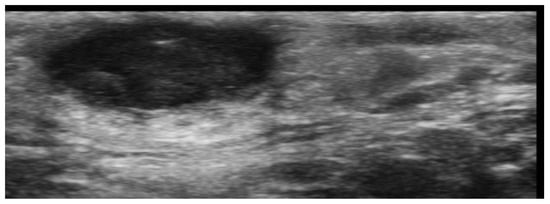

7. External-Agent-Associated Disorders

8. Neoplastic Diseases